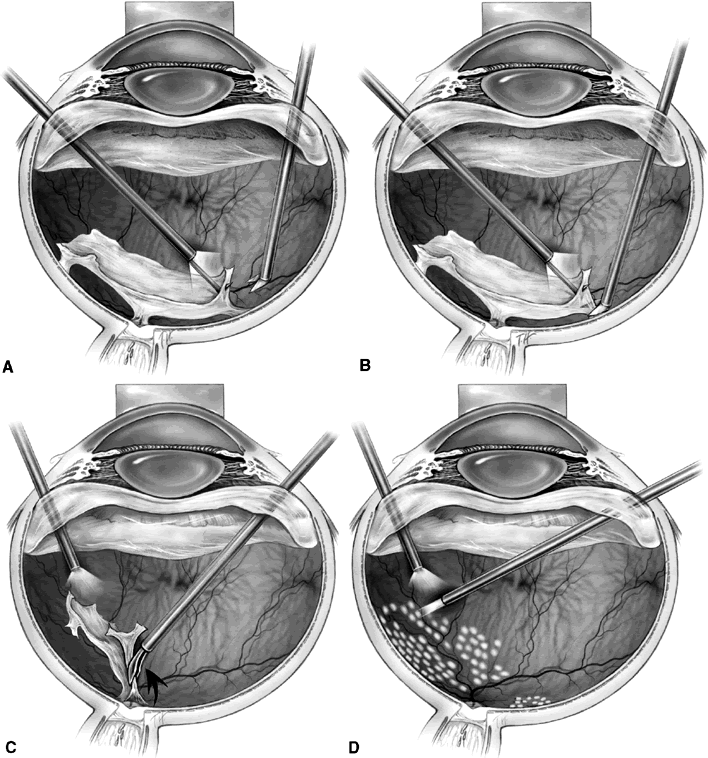

SEGMENTATION

Segmentation was the earliest method used to release retinal traction caused by preretinal fibrovascular proliferation. A core vitrectomy is first performed (Fig. 1A). Anteroposterior traction then is released by circumferentially cutting the posterior vitreous surface around the area of epiretinal proliferation (see Fig. 1B). After the anteroposterior traction has been released and the formed vitreous has been removed, the posterior vitreous surface is cut between epicenters of fibrovascular adhesion, leaving islands of fibrovascular tissue. It also may be necessary to excise bridges of fibrovascular tissue connecting epicenters, using the vitrectomy probe or intraocular scissors (see Fig. 1C). Bleeding often is a problem during segmentation because the neovascular tissue is cut far away from its origin within the retina. Intraocular diathermy often is required to control bleeding from stumps of severed fibrovascular membranes. Raising the intraocular pressure also can be used temporarily to control intraoperative hemorrhage. Finally, panretinal endophotocoagulation is applied (see Fig. 1D).

Fig. 1. A. Core vitrectomy is performed. B. Peripheral vitreous is removed, releasing all anteroposterior traction on the epiretinal membrane. C. The epiretinal membrane is segmented by cutting bridging tissue between foci of fibrovascular adhesion. D. Segmentation has been completed, and panretinal endophotocoagulation is applied.

DELAMINATION

Delamination begins similarly to segmentation with the removal of the partially detached posterior vitreous surface between the vitreous base and the edge of the fibrovascular adhesions. Using bimanual techniques, from anterior to posterior, the edge of the fibrovascular membrane is reflected using either a lighted pick, lighted forceps, the light pipe, or a tissue manipulator (Fig. 2A). This allows the epicenters of adhesion between the retina and the fibrovascular membrane to be visualized. These epicenters then are amputated at the retinal surface using horizontal scissors, membrane peeling cutter scissors, or a diamond blade (see Fig. 2B). This technique is continued until all of the fibrovascular tissue has been removed up to the optic nerve head. The membrane then can be grasped with a forceps and gently avulsed (see Fig. 2C). Unlike segmentation, after membrane dissection using delamination technique, minimal or no epiretinal tissue remains on the retinal surface (see Fig. 2D). In cases with broad areas of severe vitreoretinal adhesion, a combination of delamination and segmentation may be necessary.

Fig. 2. A. A lighted pic is used to elevate and reflect the edge of epiretinal tissue so that foci of fibrovascular adhesion can be visualized. B. Horizontal scissors are used to amputate the fibrovascular adhesion at the retinal surface. C. After the epiretinal membrane has been dissected up to the optic nerve, forceps are used to grasp the membrane and gently avulse it from the optic nerve head. D. The epiretinal membrane has been completely removed, and panretinal endophotocoagulation is applied.

“EN BLOC” VITRECTOMY AND MEMBRANE EXCISION

The en bloc technique uses the anteroposterior traction of the vitreous to elevate the edge of the fibrovascular membrane, thus serving as a “third hand.” Removal of the formed vitreous is delayed until the end of the membrane removal. Initially, the vitrectomy cutter is used to create a tunnel through the formed vitreous from the sclerotomy site to an area of vitreoretinal separation (Fig. 3A). Any subhyaloid blood then is removed through this opening. The remaining posterior vitreous surface is left attached and assists in visualizing epicenters of adhesion between fibrovascular tissue and the retina (see Fig. 3B). An illuminated pick may be used to further elevate the fibrovascular tissue, and horizontal scissors are used to amputate epicenters of fibrovascular vitreoretinal adhesion (see Fig. 3C). Hemorrhage may occur when these epicenters are cut, but since the vessels are cut close to their origin, the bleeding usually is minimal and stops spontaneously. After the posterior vitreous surface and the entire fibrovascular membrane are freed from the retina, they are removed using the vitrectomy probe (see Fig. 3D). The main disadvantage of this technique is an increased risk of iatrogenic peripheral retinal breaks caused by traction at the vitreous base, which may occur in up to 35% of cases.13 Should peripheral retinal breaks occur, they are treated with laser photocoagulation and a longacting intraocular gas tamponade, with or without scleral buckling, depending on break location and surgeon preference.

Fig. 3. A. The vitrectomy cutter is used to create a tunnel through the formed vitreous to an area of vitreoretinal separation. B. The remaining posterior vitreous exerts traction on the epiretinal membrane, assisting in visualization of epicenters of adhesion. C. Horizontal scissors are used to amputate the fibrovascular adhesion at the retinal surface. D. The posterior vitreous surface and the entire fibrovascular membrane have been freed from the retina and are removed using the vitrectomy probe.